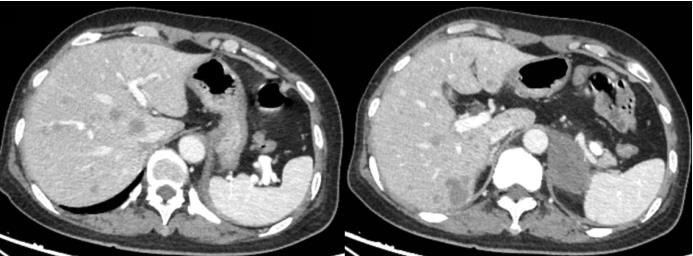

患者既往肝硬化病史,体检发现肝右叶占位,进一步增强CT检查如图示。关于该患者肝右叶占位描述正确的是

选项:

A: 发病与乙型肝炎和肝硬化密切相关

B: 大部分患者AFP升高

C: 强化方式为“快进快出”

D: 有“假包膜”

答案: 【 发病与乙型肝炎和肝硬化密切相关;

大部分患者AFP升高;

强化方式为“快进快出”;

有“假包膜”】